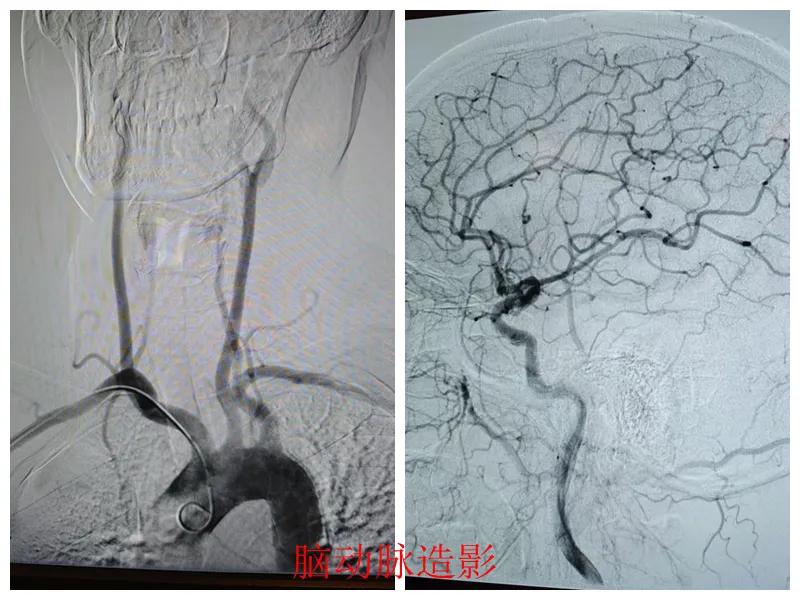

術(shù)前準(zhǔn)備完善后,在王瑾院長(zhǎng)帶領(lǐng)下,心血管內(nèi)科主任李慧新、影像科主任宋貴良、副主任醫(yī)師趙進(jìn)科等緊密協(xié)作,成功為患者實(shí)施了冠狀動(dòng)脈造影及腦動(dòng)脈造影兩項(xiàng)檢查。冠狀動(dòng)脈造影結(jié)果提示:患者右冠狀動(dòng)脈慢性閉塞,腦動(dòng)脈造影提示腦血管多支狹窄病變。